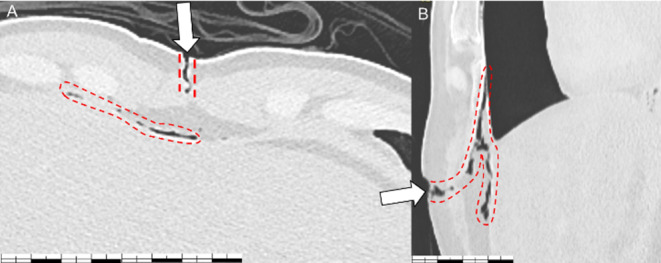

心包气肿(PPC)是指心包腔内存在气体,常导致心包填塞,死亡率高。本报告描述了一起案件,涉及一名33岁男子被发现死在离刀几米远的地方,他的衣服完好无损,没有进行任何复苏尝试。一条打了个结的围巾紧紧地围在他的脖子上,没有被勒死的痕迹。死后CT显示心包腔内气体271 ml,心脏扁平。法医检查发现两处胸部刺伤,一处刺穿心包,但没有刺穿心室,而另一处则是浅表刺伤。在没有复苏或放血的情况下,以及在窒息的情况下观察到的一些非特异性体征,支持压缩性PPC死亡的假设。这是法国第一例PPC病例报告,强调了这种实体在法医环境中的罕见性,并与文献中描述的其他未呈现相同特征的病例进行比较,指出了它所呈现的诊断困难和尸检CT在诊断中的重要性。

Pneumopericardium (PPC) is defined by the presence of gas in the pericardial cavity, often leading to cardiac tamponade and a high mortality rate. This report describes a case involving a 33-year-old man found deceased a few meters from a knife, his clothes intact, with no resuscitation attempt made. A knotted scarf was tightly fastened around his neck, without ligature mark. Post-mortem CT revealed 271 ml of gas in the pericardial cavity, with "flattened heart". The forensic examination revealed two thoracic stab wounds, one penetrated the pericardium without penetrating the heart chamber, while the second remained superficial. In the absence of resuscitation or exsanguination, and in the presence of some non-specific signs observed in the context of asphyxia, the hypothesis of death by compressive PPC was supported. This first French case report of PPC highlights the rarity of this entity in forensic settings, and comparison with other cases described in the literature which did not present the same characteristics points out the diagnostic difficulties it presents and the importance of post-mortem CT in diagnosis.